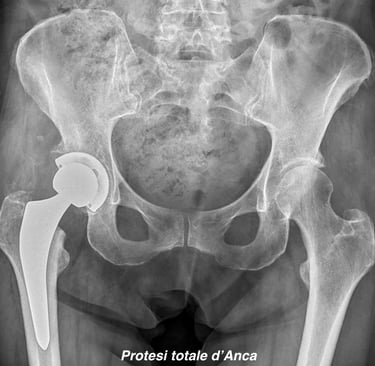

Chirurgia protesica d'anca

Impianti primari con tecnica mininvasiva ("HEROS approach")